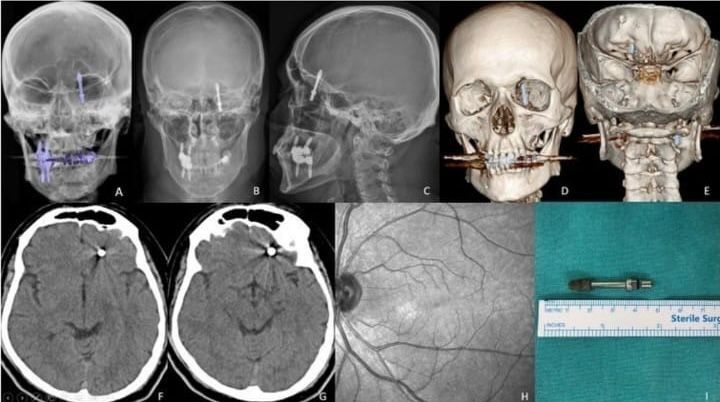

İddiaya göre, implantı çeneye yerleştirmek isteyen doktorun yanlış müdahalesi sonrası vida, Yılmaz'ın çene kemiğini delip kafatasına saplandı. Acı içinde kalan Yılmaz'ın yaşadığı baygınlık sonrası film çeken Doktor A.D., vidanın kafatasında olduğunu görünce hemen kendi aracıyla Yılmaz'ı bir hastaneye bıraktı. Hastanede çekilen tomografi sonrası gözlerine inanamayan doktorlar, 2 çocuk babası adamı hemen ameliyata aldılar.

Kendisini uyarmasına rağmen dinlemediğini ifade eden Yılmaz, "Daha sonra dişlerimi çekip, aynı gün implant uygulaması yaparken, işlemde kullandığı cihazın bozuk olduğunu sekreterine söyledi. Bu kez de işlemi eliyle yapmaya başladı. Vidayı yerleştirmeye çalışırken, aşırı yüklendiğini fark ettim. Bunu kendisine söyledim, kemik sesi geldiğini ifade ettim. Fakat bu kez de bana bunun normal olduğunu söyledi. Ama vidayı zorlarken, vida çene kemiğimi delip göz duvarının arkasından beyin omurilik sıvısının olduğu bölgeye saplandı. Ben acıdan dolayı bağırınca röntgen çektirdi" dedi

Doktorun kendisini hastaneye bırakıp kaçtığını iddia eden Yılmaz, "Durumun ciddiyetini anlayınca beni Uludağ Üniversitesi Hastanesinin Acil bölümüne getirip gitti. Burada yapılan inceleme sonrası vidanın beyin omurilik sıvısının olduğu yere saplandığı görüldü. Daha sonra uzman hekimler bir araya gelip, ameliyat için karar aldılar. Ameliyat öncesi bana hayatımı kaybedebileceğimi söylediler. Ben artık çocuklarımla helalleşip vedalaştım. Çok şükür ameliyattan sağ salim çıktım. Bu süreçlerde diş hekimi hiç bir zaman yanımda olup mağduriyetimi gidermedi, hatta ödediğim ücreti dahi geri iade etmedi. Üstüne üstelik benimle dalga geçer gibi konuştu. Bunların hepsi belgeli. Ben yetkililerden devlet büyüklerimizden bu konuyla ilgilenilmesini istiyorum. Benim iki çocuğum var. Bana bir şey olsaydı bunların hesabını kim verecekti ? Şimdi dava sürecine girdik. Kendisinden şikayetçi oldum" diye konuştu.

Öte yandan, kendisine yönelik suçlamalara daire konuşan doktor A.D., "Tıbbi bir komplikasyondan dolayı böyle bir olay gerçekleşti. Kendisi benimle ilgili bu konuda yasal yollara başvuru yaptı, fakat benim böyle bir tavrım olmadı" ifadelerini kullandı. Öte yandan Yılmaz'ı sağlığına kavuşturan doktorların başarılı ameliyatı, Amerika'da literatüre girip dergilere konu oldu.